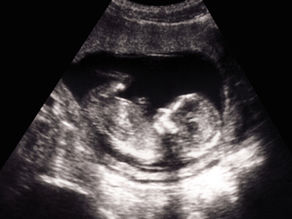

Akušerstvo

Praćenje trudnoće od ranih nedelja uz individualni pristup i jasno objašnjenje nalaza.